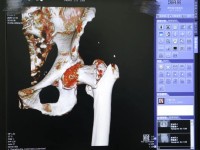

入院完善相关检查:骨盆平片清晰提示左股骨粗隆间骨折;左髋关节CT+三维重建进一步明确诊断为左股骨粗隆间粉碎性骨折(Evans-Jensen IB型),同时发现左髋关节退行性变及周围少量积液。结合老人既往病史及术前相关检查,中医诊断:骨折病(气滞血瘀证) ;西医诊断为:1. 左股骨粗隆间粉碎性骨折(Evans-Jensen IB型);2. 左髋关节骨关节炎;3. 慢性支气管炎伴感染;4. 多发性脑梗死;5. 冠状动脉粥样硬化性心脏病。